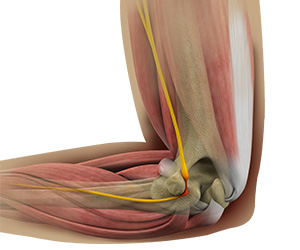

Ulnar Nerve Release

Ulnar nerve release, also known as ulnar nerve decompression, is a surgical procedure to treat a medical condition called ulnar nerve entrapment.

Cubital Tunnel Syndrome

When the elbow is bent, the ulnar nerve can stretch and catch on the bony bump.

Cubital Tunnel Release (Medial Epicondylectomy)

Cubital tunnel release is a surgical procedure to correct cubital tunnel syndrome.